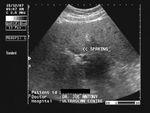

Diffuse fatty liver with focal fatty sparing

In these 3 ultrasound images there is diffuse fatty change of liver with focal fatty sparing in the periportal region, just anterior to the porta hepatis. This is a typical site of focal fatty sparing. This is seen as a small hypoechoic region. Images taken with a Pie Scanner 100 Falco, by Dr. Joe Antony.